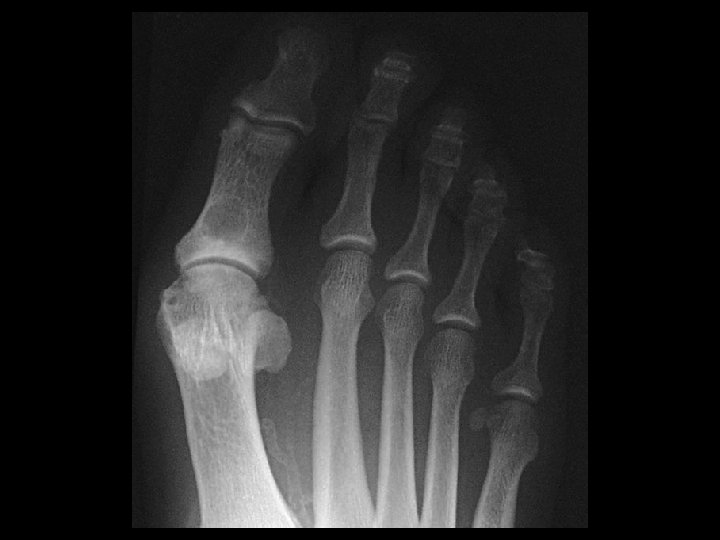

Gout • Findings: – Large erosions with overhanging margins at the great toe MTP joint – Dense periarticular swelling – Sparing of the joint space • ddx: – NONE! – This is an Aunt Minnie!